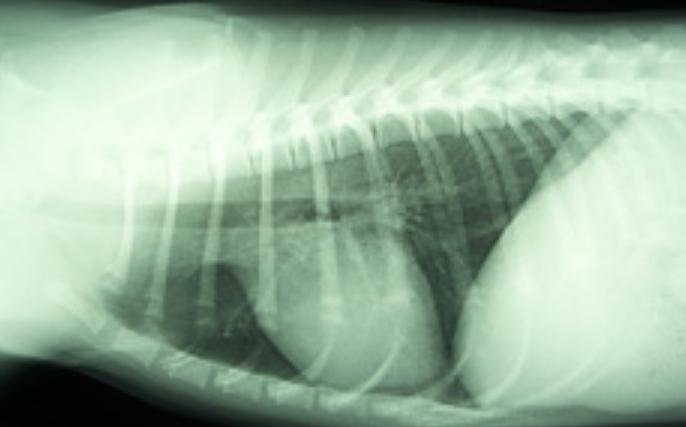

通过体格检查后,依序进行影像学检查,分别是X射线检查、钡餐造影。

X光可显示肺部显影是否异常,肺部区域有没有被压迫的情况。

钡餐造影会先服用硫酸钡进行X光拍摄,去检查口服钡餐后是否都聚集在肺部。